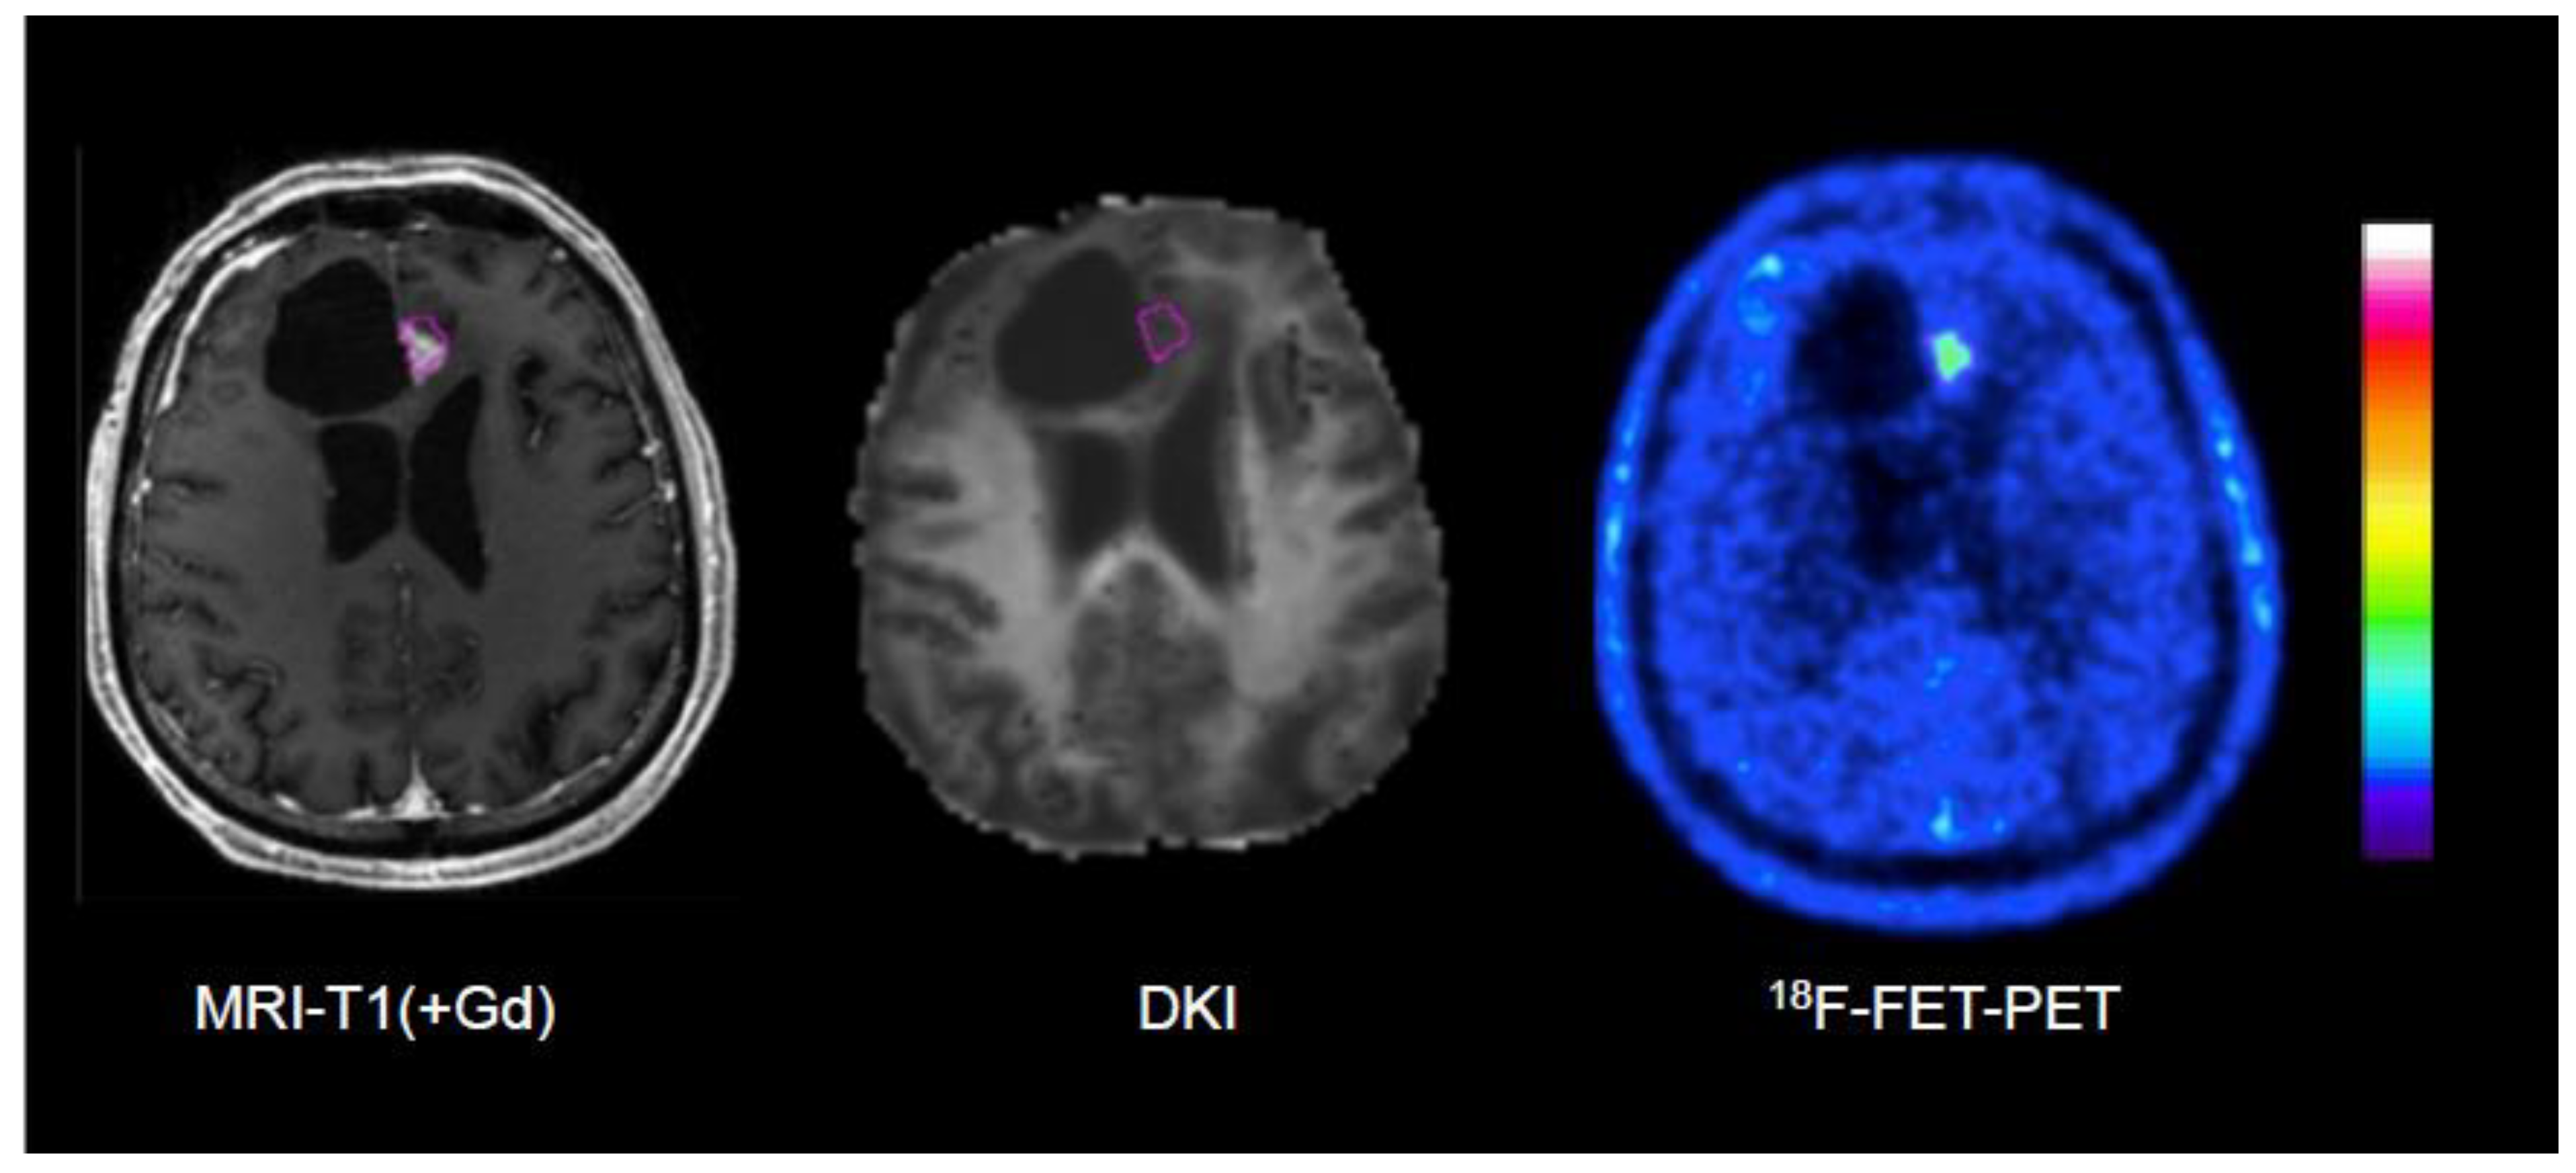

- D’amore, F.; Grinberg, F.; Mauler, J.; Galldiks, N.; Blazhenets, G.; Farrher, E.; Filss, C.; Stoffels, G.; Mottaghy, F.M.; Lohmann, P.; et al. Combined 18F-FET PET and diffusion kurtosis MRI in posttreatment glioblastoma: differentiation of true progression from treatment-related changes. Neuro-Oncology Adv. 2021, 3, vdab044, . [CrossRef]

| D’Amore et al. [108] | 2021 | 18F-FET | DWI, DKI | Tumor recurrence in pretreated gliomas | 32 | Verification by surgery (12) and clinical follow-up (20), DKI evaluation guided by 18F-FET PET | Best AUC by combination of static 18F-FET PET and DKI (0.97) versus 18F-FET PET (0.77) or DKI alone (0.87) |